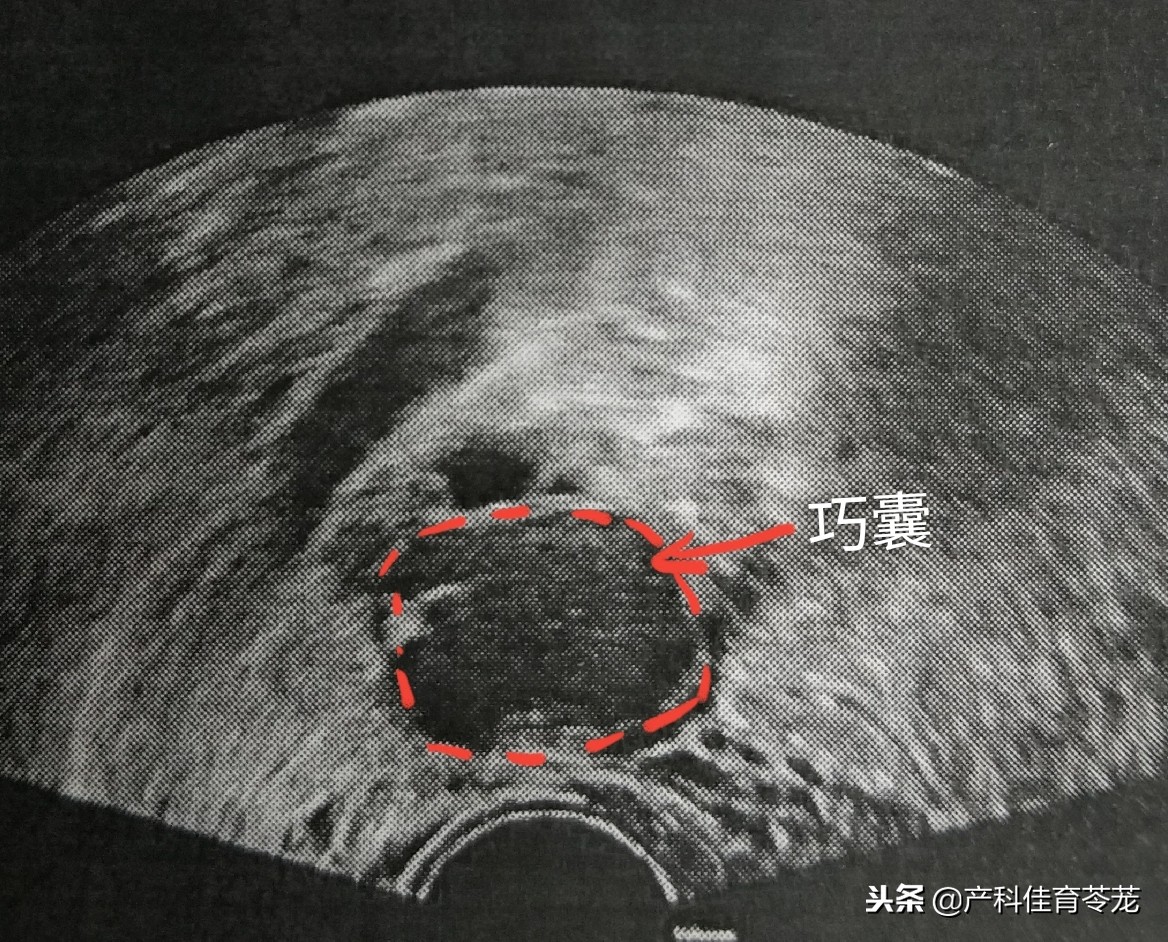

1、卵巢巧克力囊肿(内膜异位囊肿)

子宫内膜组织异位于卵巢,这些异位灶反复出血形成囊肿,里面是暗褐色粘糊状陈旧性血液,像巧克力,故又称为巧克力囊肿。

这种囊肿B超诊断准确率很高:

同样里面是液体,但B超下看到的不是透亮的,里面有密集的细点状回声,说明不是单纯的一包“水”,而是有血。

巧克力囊肿的女性多数有痛经的症状,严重的会引起不孕,如果发生破裂会引起突发腹痛。